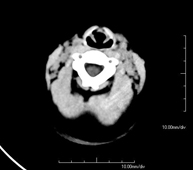

- Neurorradiología- TC Cráneo Prueba radiológica que consiste en obtener imágenes del cráneo de alta definición anatómica (tronco cerebral, cerebelo, cerebro, calota craneal, etc.), mediante el empleo de un equipo de TC (Tomografía Computarizada).Indicaciones: traumatismos, cefalea, trastornos de la memoria, pérdida de fuerza súbita en una extremidad o mitad del cuerpo. Prueba radiológica que consiste en obtener imágenes del cráneo de alta definición anatómica (tronco cerebral, cerebelo, cerebro, calota craneal, etc.), mediante el empleo de un equipo de TC (Tomografía Computarizada).Indicaciones: traumatismos, cefalea, trastornos de la memoria, pérdida de fuerza súbita en una extremidad o mitad del cuerpo.

- Pediatria- TC de crani Prova radiològica que consisteix en obtenir imatges del crani d'alta definició anatòmica, mitjançant l'ús d'un equip de TC (Tomografia Computeritzada). Indicacions: cefalea, estudi de tumors, traumatisme cranial. Prova radiològica que consisteix en obtenir imatges del crani d'alta definició anatòmica, mitjançant l'ús d'un equip de TC (Tomografia Computeritzada). Indicacions: cefalea, estudi de tumors, traumatisme cranial.